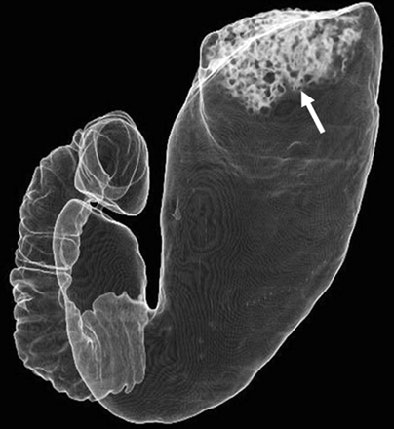

| CT gastrographic image of 64-year-old man in left posterior oblique (LPO) position. Transparent volume-rendering technique shows good distension of stomach except in gastric fundus. Note bubbly fluid (arrow, B) in fundus. Fig. 1B. Kim SE, Lee JM, Han JK, Lee JY, Shin KS, Choi IC. "Effect of Adjusted Positioning on Gastric Distention and Fluid Distribution During CT Gastrography" (AJR 2005; 185:1180-1184). |

LPO's advantage was even more pronounced in terms of residual fluid, with mean scores for the proximal and distal antrum together significantly larger among the LPO patients (p < 0.03) than the supine group. LPO trended higher for the remaining segments but the differences were not statistically significant (p > 0.05). The total score for both parameters in the LPO group was 3.6 ± 0.8 (mean ± SD) compared to 3.2 ± 1.0 for the supine group, and the difference was statistically significant (p < 0.0001).

"Unlike double-contrast barium studies in which imaging can be performed in multiple projections to allow the fluid to redistribute, scanning for CT gastrography should be limited to only one or two projections -- that is, the supine or LPO position and the right decubitus position," the authors wrote. "Positioning toward one's back in the LPO position just after turning onto one's left side can shift fluid in the gastric antrum to the gastric fundus, and subsequently allow a clean image of the lower gastric portion to be obtained."

The results showed that the mean scores for gastric distension in most stomach segments were larger in the LPO patients than the supine group, and were statistically significant in the lower three segments, including the lower body, proximal antrum, and distal antrum (p < 0.004), but not statistically significant for the remaining three segments (p > 0.05).